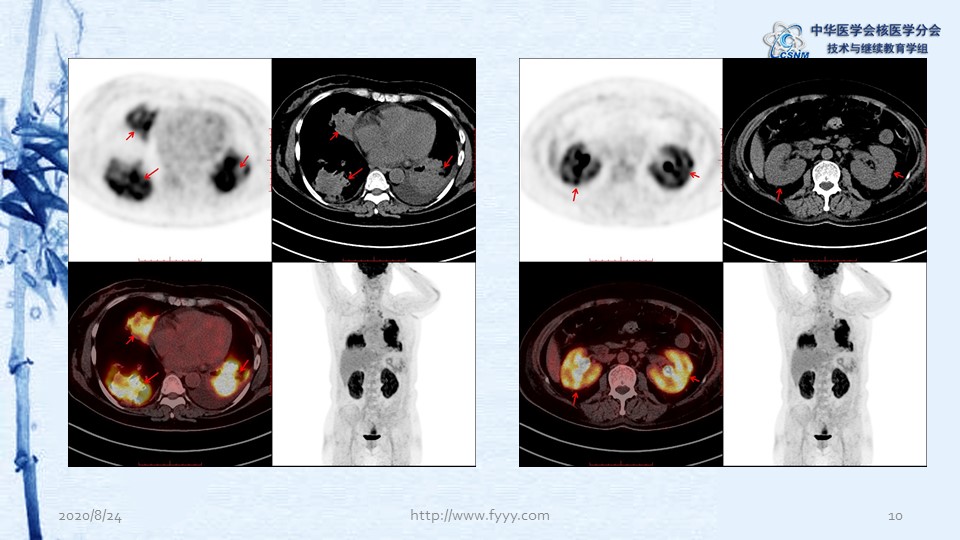

病例82:肉芽肿性血管炎PET-CT显像一例-【CSNM继教学组】郑山 福建医科大学附属第一医院